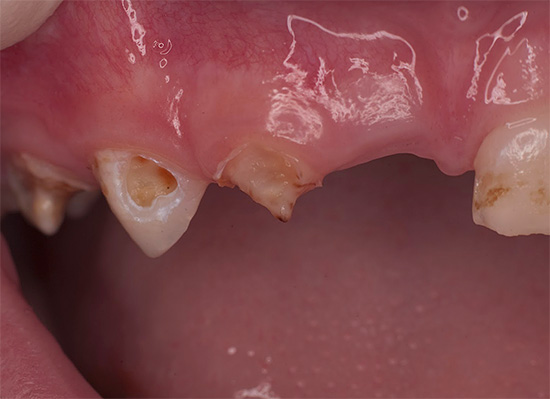

La foto sotto mostra un altro esempio di corsa carie dei denti decidui in un bambino:

Molto spesso, questa situazione si osserva nei bambini che hanno avuto malattie infettive acute, soffrono di varie malattie croniche e hanno difetti cardiaci congeniti.

Un'alta prevalenza di carie generalizzata si osserva nei bambini con tonsillite, scarlattina, che soffrono di reumatismi cronici, glomerulonefrite, malattia di Little, sindrome di Down e malattia del marmo.